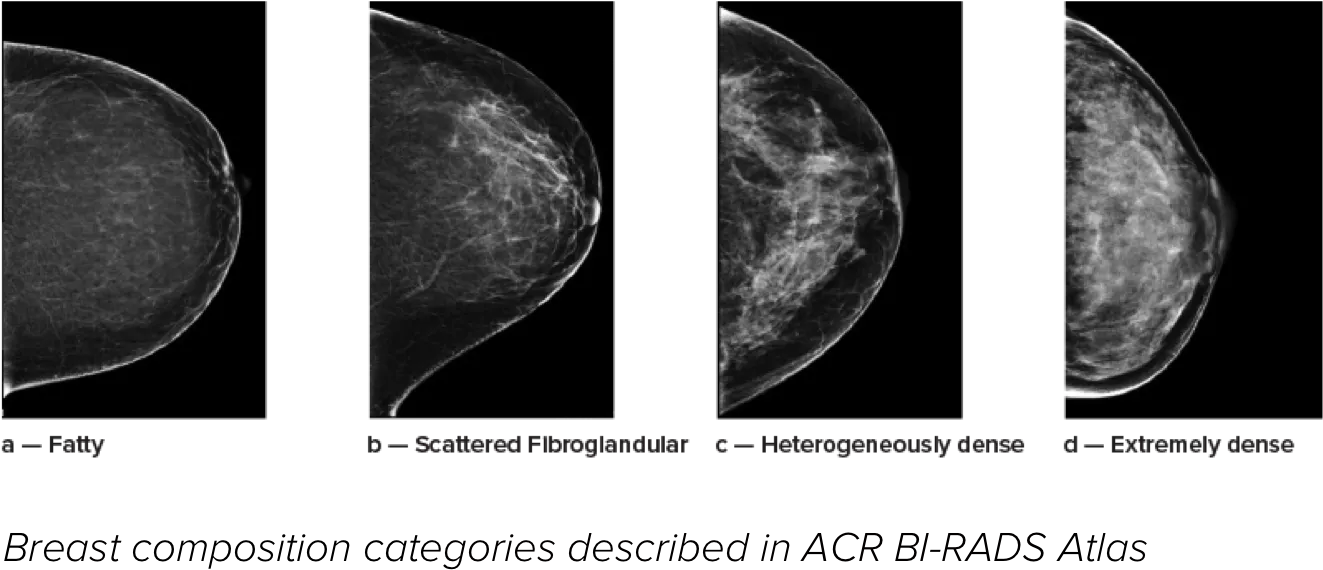

Higher breast density is known to increase a woman’s risk for breast cancer.1 The need for accurate, unbiased analysis is therefore critical. Powered by machine learning, Quantra technology software analyses both 2D™ and tomosynthesis images for distribution and texture of parenchymal tissue. It categorises breasts in four breast composition categories consistent with guidance from the American College of Radiology (ACR) BI-RADS Atlas 5th Edition.2

8. Breast composition categories as described in ACR BI-RADS Atlas.